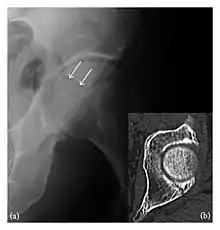

Occult osseous injuries may result from a direct blow to the bone by compressive forces of adjacent bones against one another or by traction forces during an avulsion injury. Lesions in the tibial plateau, hip, ankle, and wrist are often missed. In a tibial plateau fracture, any disruption of the posterior and anterior cortical rims of the plateau should be sought. Impaction of subchondral bone will appear as an increased sclerosis of the subchondral bone (Figure 1). In the hip, posterior acetabular fractures also present subtle radiographic findings. The acetabular lines should then be carefully examined keeping in mind that the posterior rim, which is harder to see on X-rays, is more frequently fractured than the anterior rim (Figure 2). In the wrist, detection of carpal bone fractures is often challenging, with up to 18% of scaphoid fractures radiographically occult. Carpal fractures, especially the scaphoid, are associated with the risk of avascular necrosis. In apparently normal wrist radiographs from symptomatic patients, if there is history of a fall on an outstretched hand with pain in the anatomic snuffbox, suggesting scaphoid injury, the initial examination with posteroanterior, lateral, and pronation oblique views must be complemented by other specific views such as supination oblique and the "scaphoid" view A careful examination of cortices for evidence of discontinuity or offset and cancellous bone for lucency is necessary (Figure 3).[1]

Figure 2: Posterior acetabular fracture in a 49-year-old woman presenting with hip pain after a fall. (a) Anteroposterior radiograph of the left hip shows a radiolucent line through the posterior acetabular wall (arrows). (b) Axial CT confirms the acetabular fracture (arrow).[1]